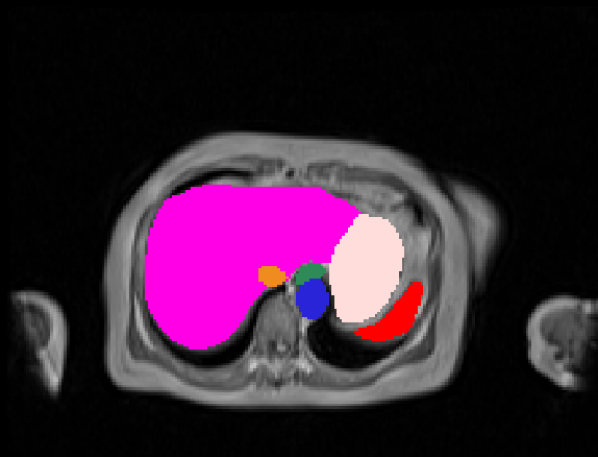

Manual Labels for Verification. We design a mechanism to validate these collected labels by humans. To do so we collect manual labels from 3000 2D image from 300 MRI samples for 10 abdominal organs (UKBOB-manual). These manual labels (see examples in Figure 2) act as a validation for the large UKBOB dataset. On these labels, the UKBOB automatic labels obtain an average Dice Score of 0.891 (see Table 3). Furthermore, we verify the spine labels of UKBOB using previously collected manual labels of 200 3D spine labels [5]. We show an example in Figure 1 and we see how the new collected labels match the manual labels in the spine with a total Dice score of 0.811, indicating accurate labels. We discuss in Section 5.1 another mechanism for verifying the labels by zero-shot generalization of trained models to other similar datasets that has manual labels.

| Input | Prediction | Entropy Map |

3.3 Entropy Test-Time Adaptation (ETTA)

This process adapts the model to the test sample by encouraging confident (low-entropy) predictions, thereby refining the segmentation output. The adaptation is efficient as it involves updating a small subset of parameters and can be performed online during inference. ETTA leverages the entropy of the network’s predictions (Figure 5) to guide the adaptation, improving robustness to domain shifts and label noise.